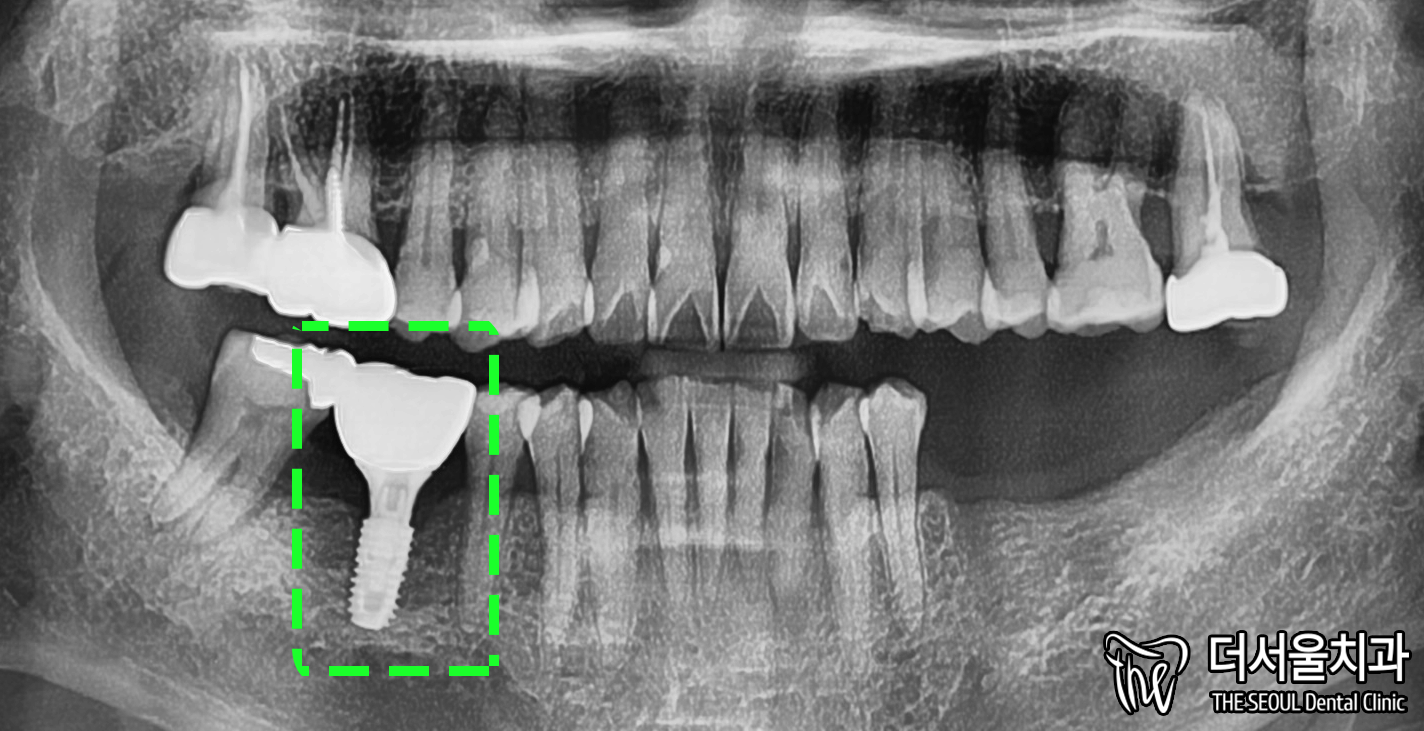

어버트먼트와 크라운을 씌우며

46번은 모든 과정이 다 끝났습니다.

윗니와 교합이 잘 이뤄질 수 있도록

꼼꼼히 체크하며 조정 완료했습니다.

이제 왼쪽만 남겨두고 있죠?

그 과정까지 함께 보겠습니다.

5. 30번대 시작

CT 촬영본을 통하여

해당 부위는 어떤게 부족한지

정확히 알 수 있습니다.

이 데이터를 기반으로 디지털 프로그램으로

모의 수술을 해볼 수 있구요.

결과값에 따라 주의할 점은 조심하고

실제로 적용해줍니다.

성남 치과 의원은

뼈이식할 부분에 재료를 채워넣고

픽스처를 식립했습니다.

이제 뼈와 잘 붙을 수 있도록

주변에 자극을 덜 받도록 해야겠죠?

픽스처 위에 보면 뭔가 올라와있습니다.

이것을 ‘힐링 어버트먼트’라 부르는데요.

쉽게 알려드리면 일종의 ‘보호캡’입니다.

오토바이를 탈 때 헬멧을 쓰듯이 말이죠.

이렇게 회복할 수 있도록 충분히 기간을 가져줍니다.